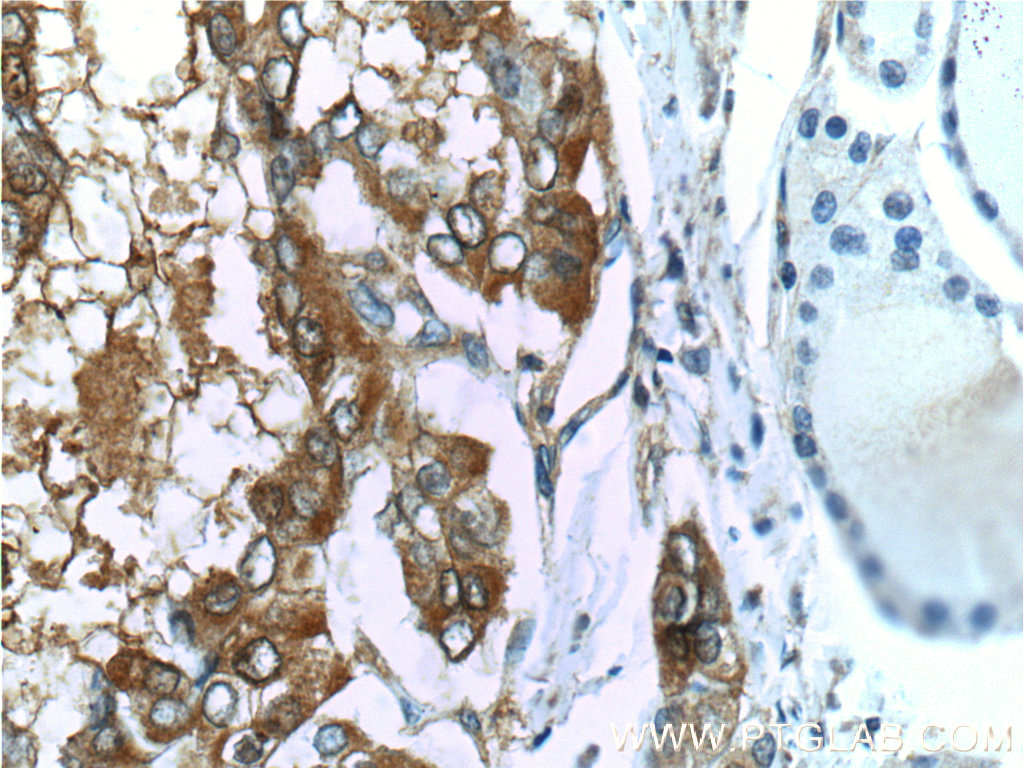

| Positive IHC detected in | human thyroid cancer tissue, human colon tissue, human ovary tumor tissue Note: suggested antigen retrieval with TE buffer pH 9.0; (*) Alternatively, antigen retrieval may be performed with citrate buffer pH 6.0 |

| Immunohistochemistry (IHC) | IHC : 1:1000-1:4000 |